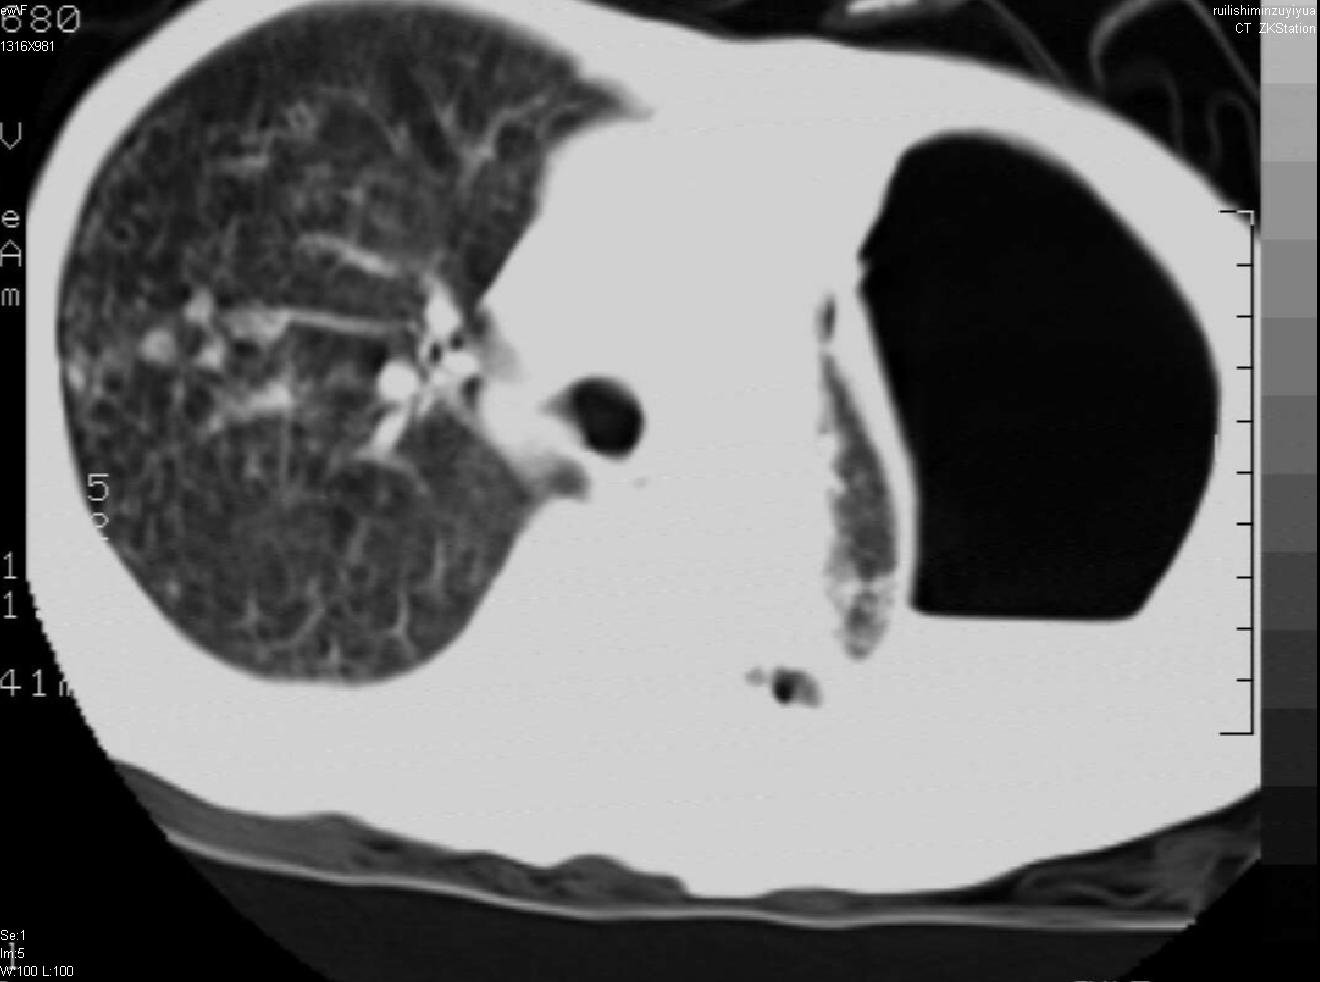

以下是引用天南地北在2007-6-11 23:32:00的发言:[br]1:左侧肺毁损(结核性)伴感染(多发空洞伴液平面)。[br]2:右肺继发型肺结核。

以下是引用avril在2007-6-12 1:17:00的发言:[br]1、左肺毁损。[br]2、左肺多发肺大泡伴自发性气液胸形成。[br]3、右肺继发型结核。